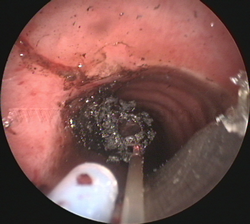

Fotorresección

con láser |